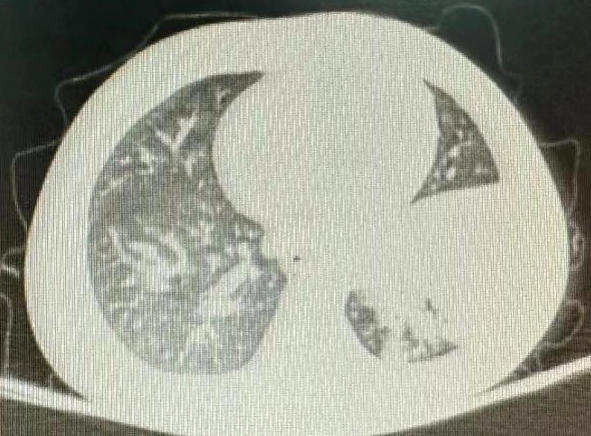

2岁男童,因“发热、咳嗽1周,加重1天”入院。院前曾查肺部CT提示左肺炎症,并在院前治疗5天,热不退,后又治疗3天,仍有高热,立即复查肺部CT示大叶性肺炎较前加重。